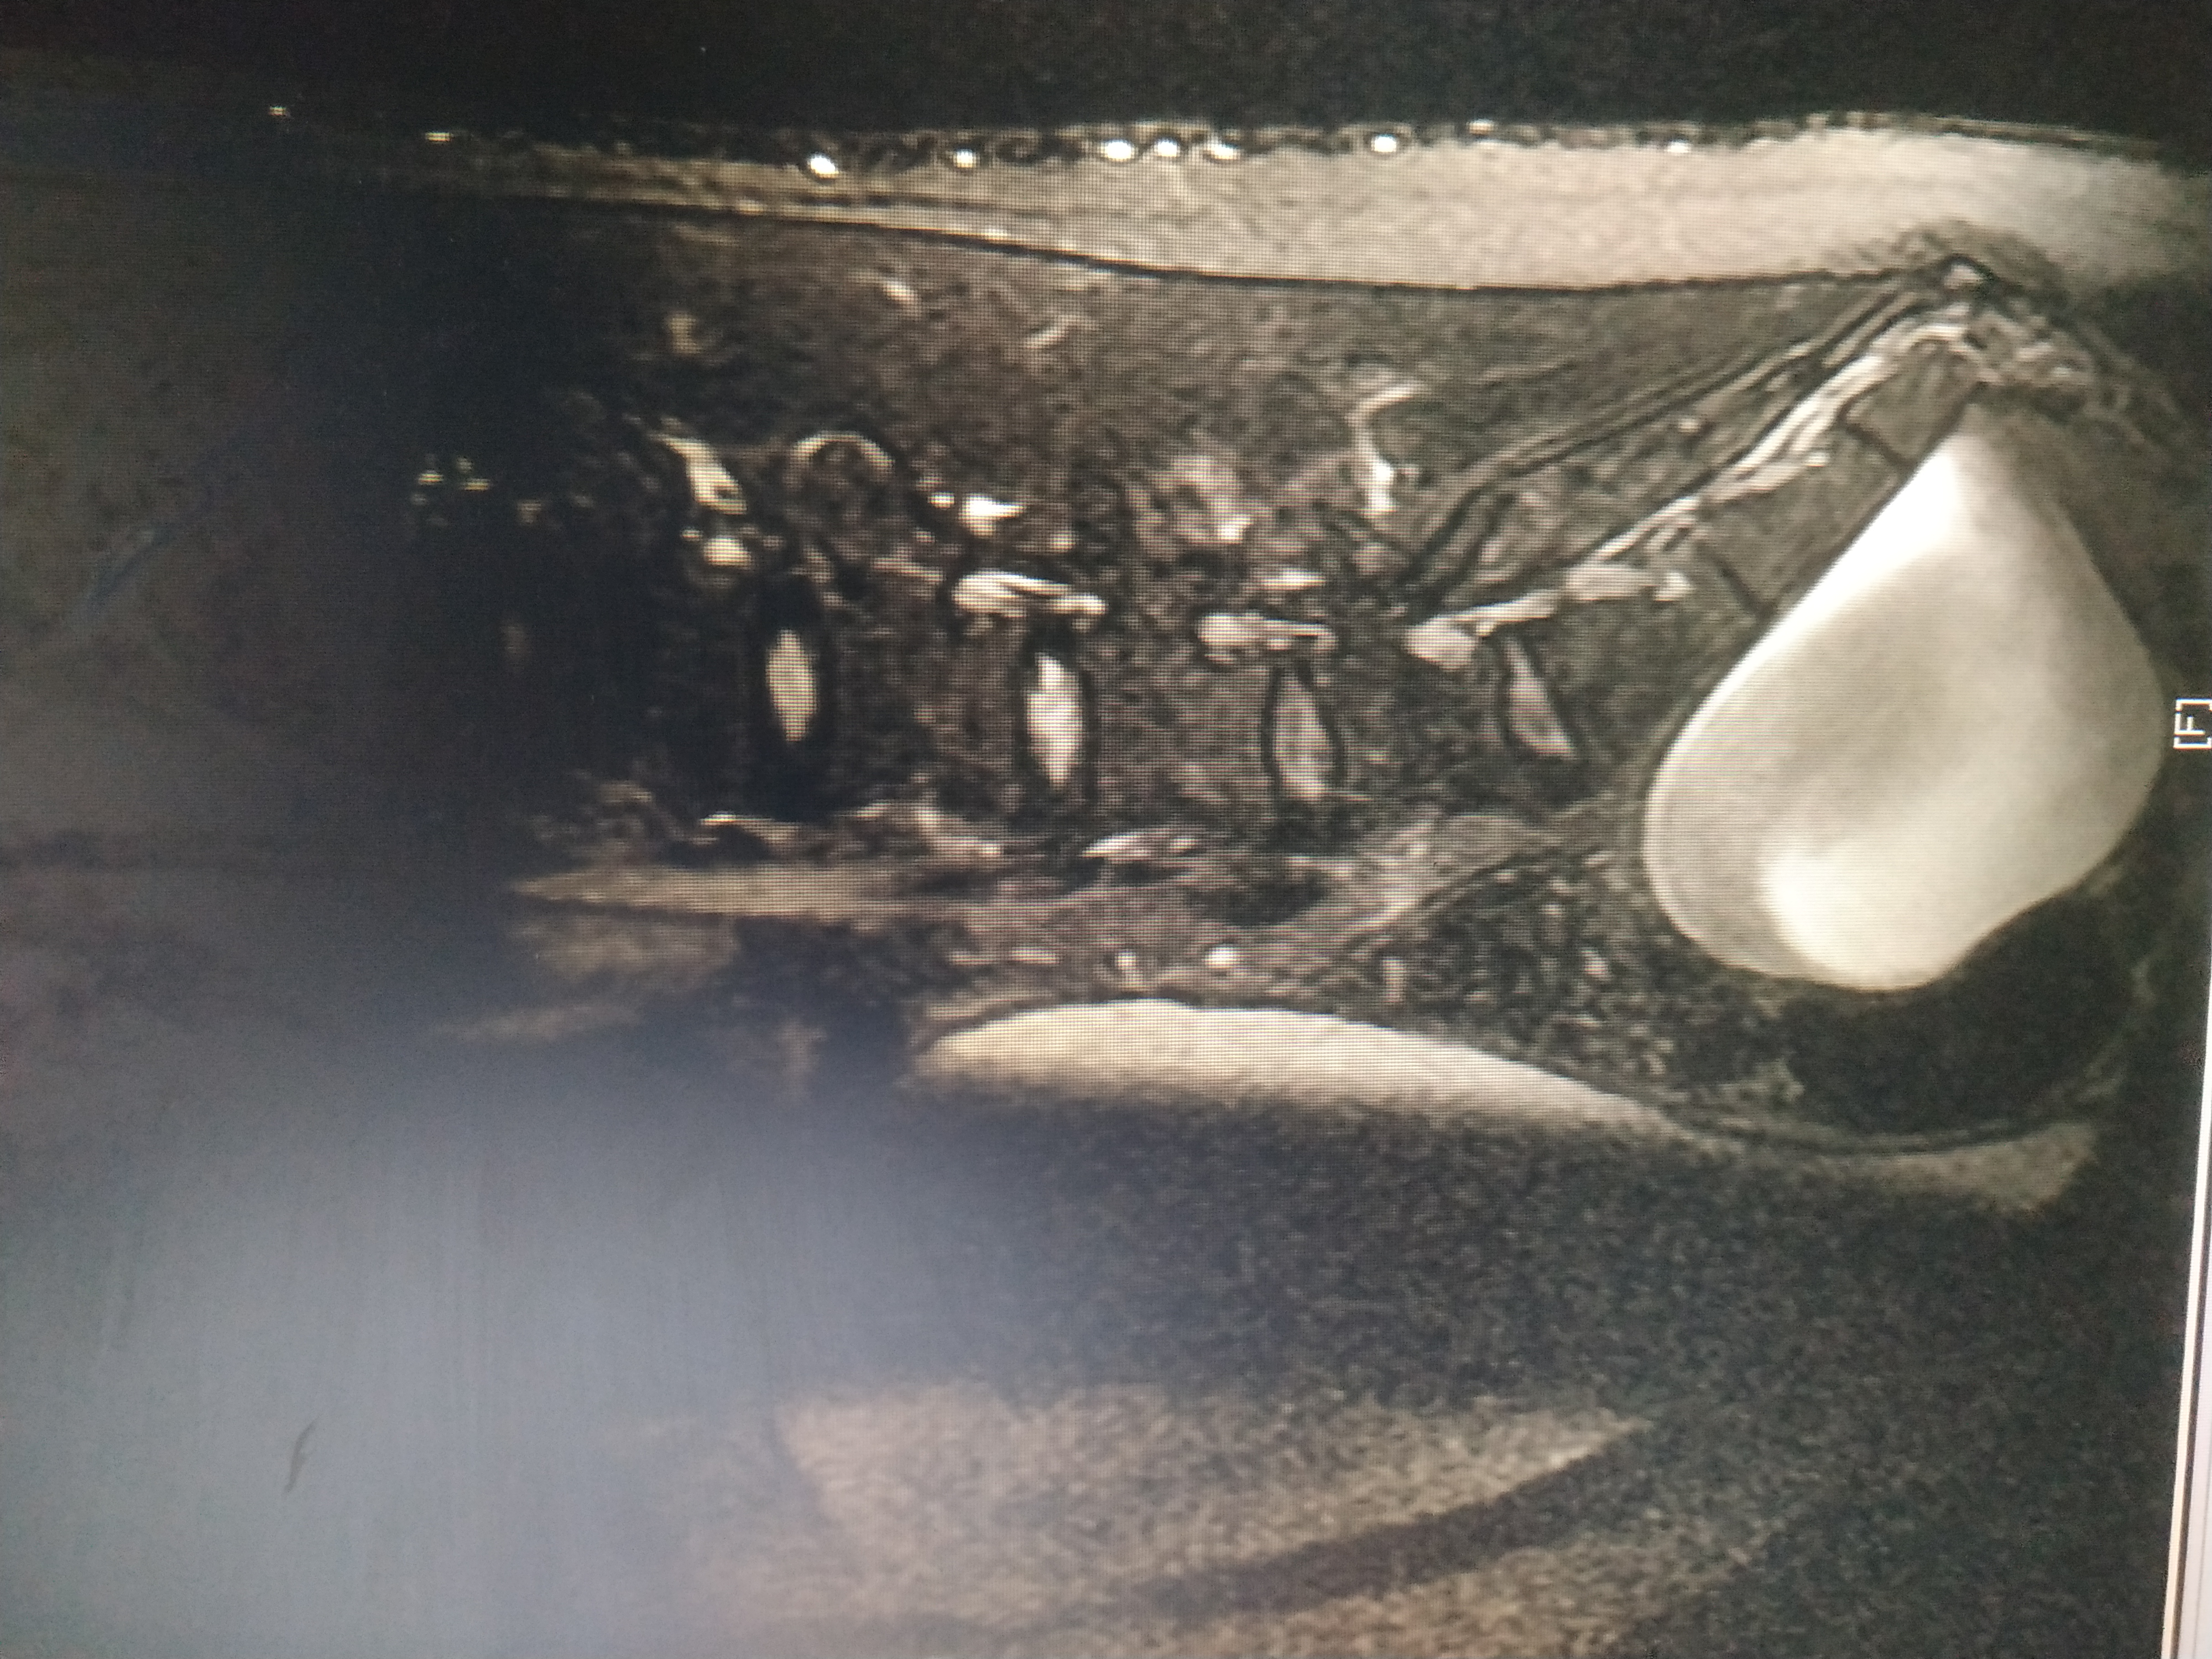

Здравствуйте! Скажите пожалуйста, оперировал ли кто нибудь из нейрохирургов в вашей клинике менингоцеле? Полный диагноз : менингоцеле крестцово - поясничного отдела s2-s5, Спинномозговая вентральная грыжа 11 см идущая в полость малого таза с компрессией мочевого пузыря, предстательной железы и дизурическими расстройствами. Мне 29 лет